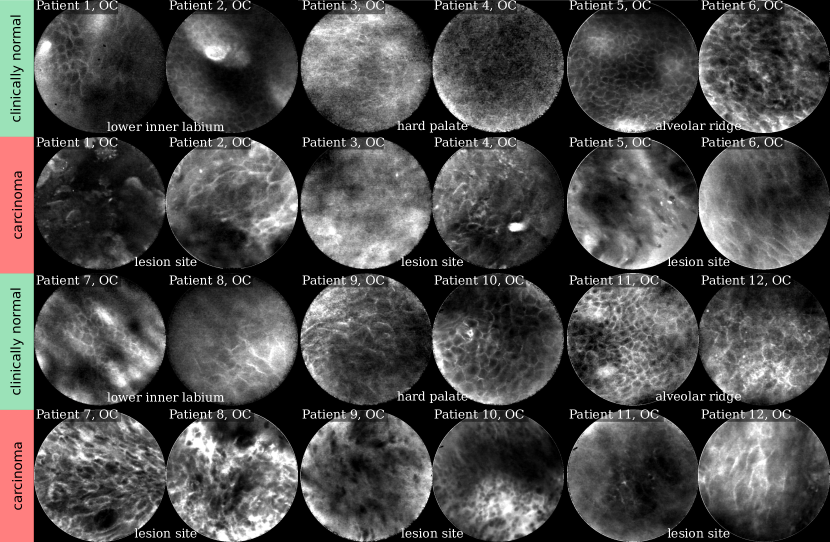

Refer to caption

Figure 2: Selected CLE Images acquired from the oral cavity (OC). First and third row show images from clinically normal regions, second and fourth row show images from lesion sites later diagnosed as OSCC.

Comparing the images in Figures 2 and 3, for clinically normal (and presumably healthy) tissue we find a large difference in contrast for some regions. While for images acquired from the alveolar ridge (rows 1 and 3, columns 5 - 6 in Fig. 2) and the vocal folds (top row in Fig. 3), contrast is generally good and cell outlines can be clearly spotted for most images, we find a much broader spread in image quality for images acquired at the hard palate and the lower inner labium (rows 1 and 3, columns 1-4 in Fig. 2).

In CLE images, the raw pixel value represents the optical (fluorescent) response to the laser light excitation. The optical receiver and analog to digital converter of the CLE scanner in use have a broad dynamic response. Thus, all images presented in this work and also in the CellVizio software are automatically compressed in their value range to fit the 8 bit gray level range of today’s screens and to increase contrast for the viewer. The median raw pixel value, however, is indicative of the amount of fluorescent light that was picked up by the scanner, and as such also related to the signal-to-noise-ratio of the image. We use median, as it is more robust to the (typically sparsely distributed) very bright areas representing micro-vessels filled with contrast agent, as e.g. in row 2, column 4 of Fig. 2. We evaluated the median raw pixel value on images for all anatomical regions separately (see Fig. 4). For images acquired from the hard palate and the lower inner labium, we find a significantly different distribution than for both other anatomical locations, in that the prevalence of images with low median value (and thus likely low SNR) is much higher for these regions. In contrast, the vocal fold and alveolar ridge area both have a rather low amount of noisy images. This underlines our visual observation derived from the representative images in Fig. 2.